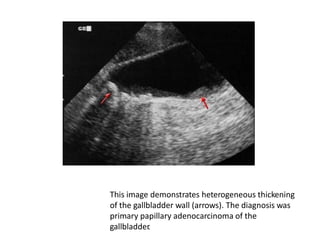

This image demonstrates heterogeneous thickening

of the gallbladder wall (arrows). The diagnosis was

primary papillary adenocarcinoma of the

gallbladder.